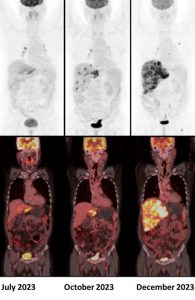

A 50 year old male, diagnosed with metastatic cholangiocarcinoma, was started on Durvalumab. Given below are his serial 18F-FDG PET/CT scans. Which of the following statement is correct ?

Answer: C. Scan findings are suggestive of confirmed progressive disease (iCPD).

According to the iPERCIST, complete resolution of FDG uptake within the target lesion is considered a complete response. A more than 30% decrease in the target tumor FDG SULpeak is considered as partial response. A more than 30% increase in FDG SULpeak or the advent of new 18F-FDG-avid lesions is considered an unconfirmed progressive disease, which should be confirmed by a second follow-up scan 4-8 weeks later. If progression was observed in the second scan, it is then labelled as a confirmed progressive disease. If there is no significant interval change (less than 30% increase or decrease in SULpeak with no new lesions), it is labelled as stable disease. If there is more than 30% decrease in the target tumor FDG SULpeak, then it is considered as partial response (2).